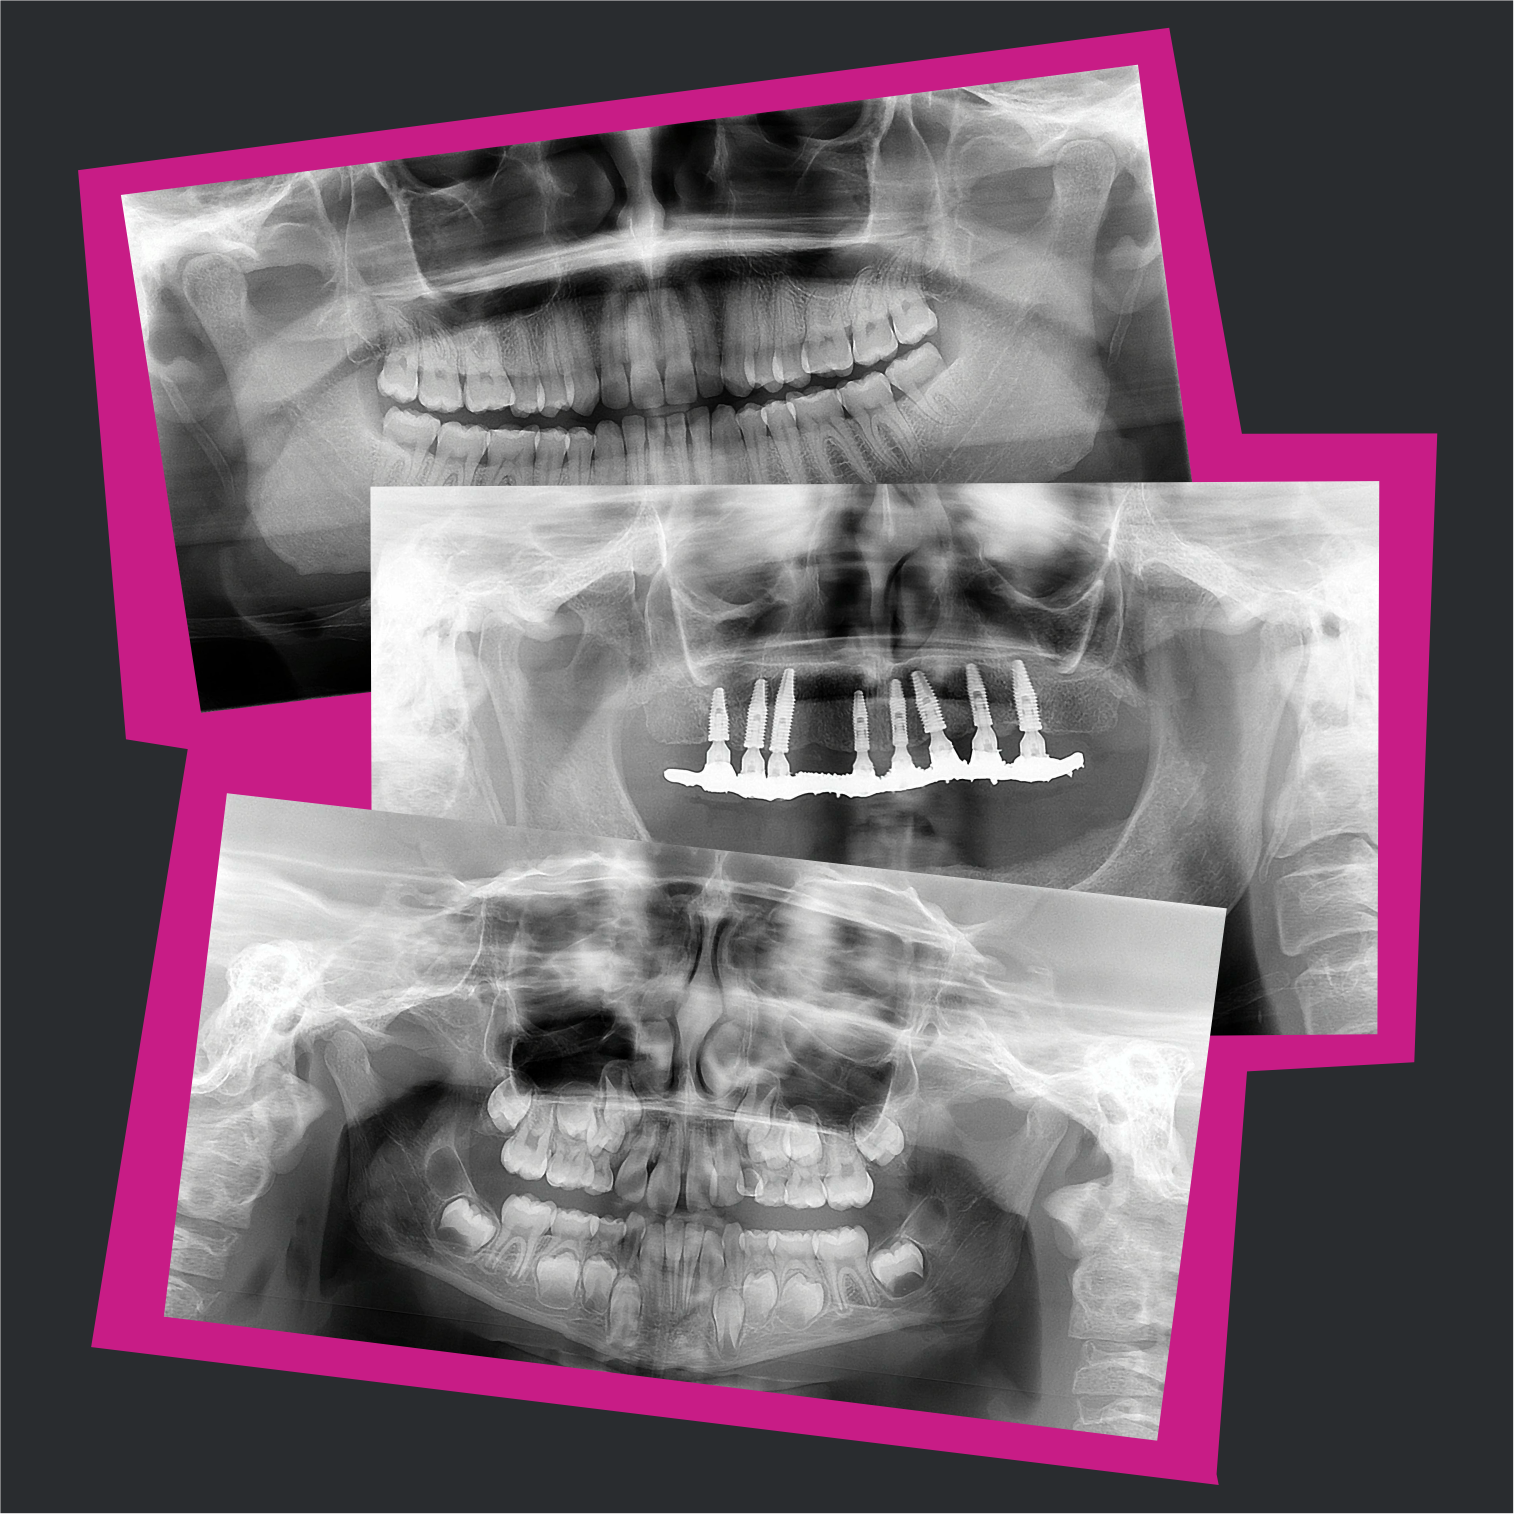

Bem-vindo ao curso Radiografia Panorâmica Como Você Nunca Viu, o guia completo sobre radiografia panorâmica para acadêmicos de Odontologia, cirurgiões-dentistas, técnicos e tecnólogos em Radiologia. Aprenda tudo o que é preciso saber sobre radiografia panorâmica, o exame mais pedido e mais realizado em Odontologia.

A radiografia panorâmica continua sendo atual, pois é o exame de imagem mais pedido e realizado em Odontologia. Além disso, é o exame inicial por excelência, a grande maioria dos dentistas não começa um tratamento sem ter em mãos uma radiografia panorâmica do paciente.

Anatomia radiográfica e variações anatômicas

Interpretação radiográfica